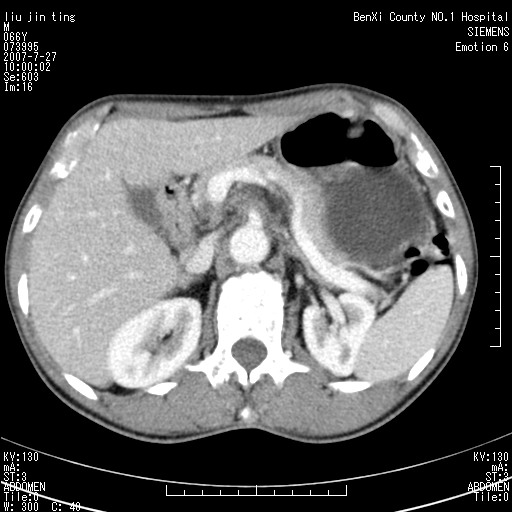

腹痛,背痛,无恶心呕吐,不黄,彩超示胰腺钩癌,ct扫描病灶平扫30-40hu,增强后动脉期40--60hu,静脉期50-68hu,真的是钩突上的么?您要试一试么?

动脉期

静脉期